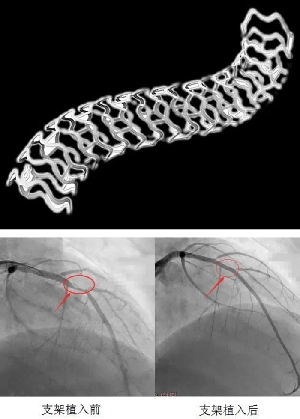

突破!我院成功完成首例生物可吸收支架植入術

患者,男性,32歲,因“急性下壁心肌梗死介入治療后1年伴胸悶不適1月”就診,收住心血管二病區(qū),診斷為“不穩(wěn)定性心絞痛、陳舊性心肌梗死、冠脈支架術后”。患者入院后完善術前準備,給予冠脈造影檢查示:右冠脈支架通暢,未見狹窄,左冠脈前降至近端可見90%局限性狹窄??紤]患者年輕,病變?yōu)锳型病變,參考患者家人意愿,決